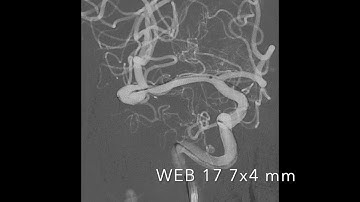

MicroVention WEB System Animation